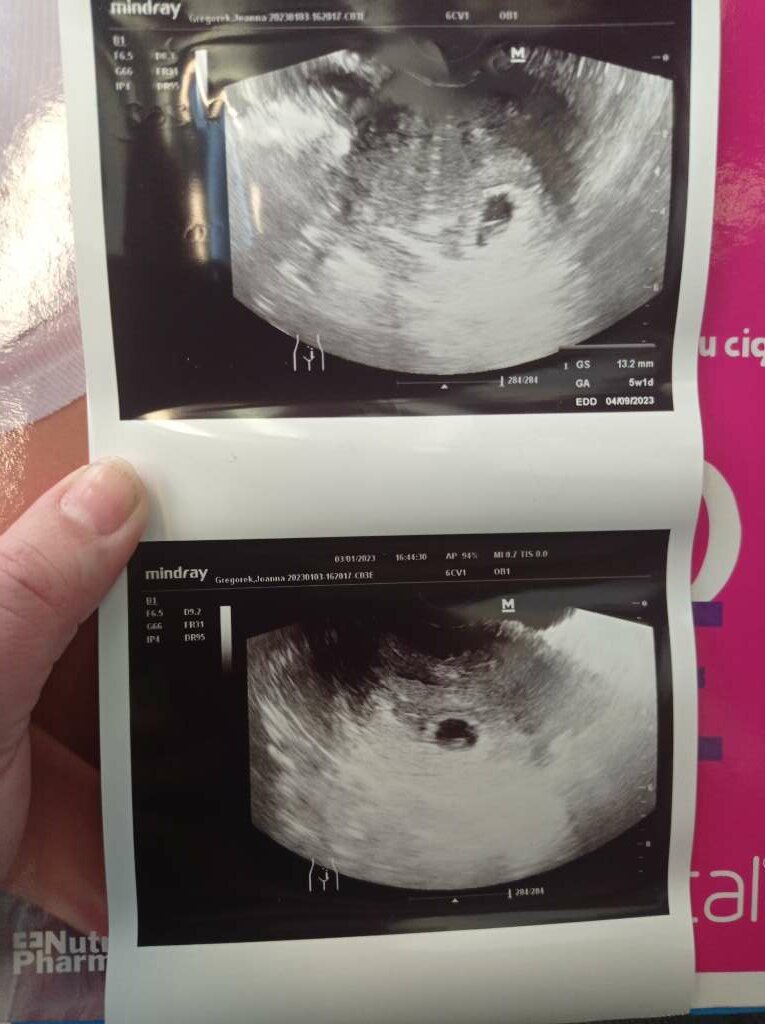

Zrobil pomiary. Pecherzyk wielkosci 13,5 mm jesli dobrze pamietam. Za dwa tygodnie mam przyjsc zalozymy karte bo wtedy napewno bedzie juz bic serduszko :).

• c7fea7d1-d7fe-406e-bcb0-3ccd4b6b8f96.jpeg

c7fea7d1-d7fe-406e-bcb0-3ccd4b6b8f96.jpeg

93,3 KB · Wyświetleń: 148